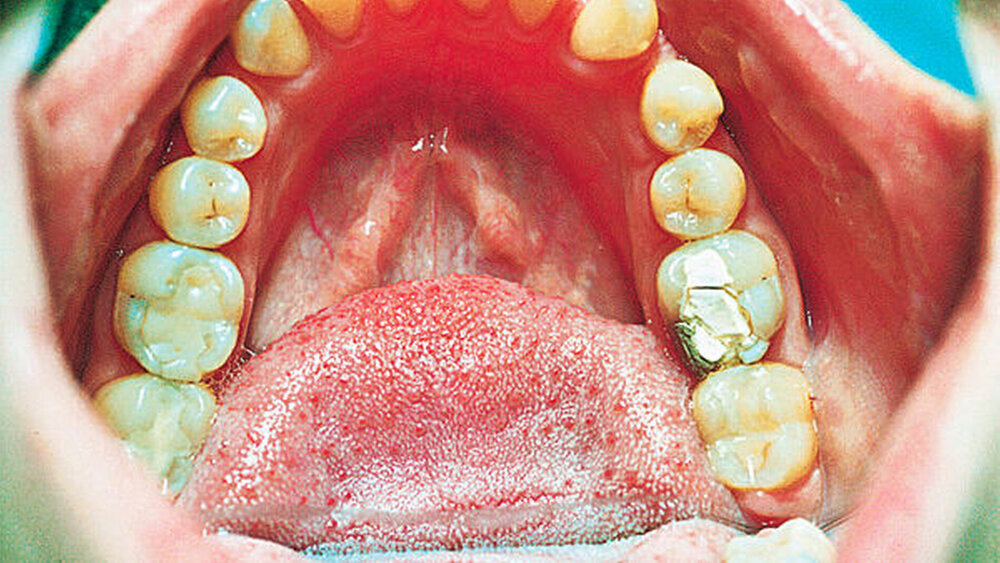

Das Verfahren war im Jahr 2002 noch nicht etabliert. Doch wider allgemeines Erwarten gestaltete sich die Einheilung problemlos. Nach einem Jahr zeigte sich der Zahn 28 – nun im Unterkiefer an Position 36 – kaufunktionell voll integriert: Die Abbildungen 1 bis 4 veranschaulichen die Situation im Jahr 2002 [erschienen in: „Wenn Weisheitszähne zum 6-er werden“, H.-W. Bertelsen, ZM 92 Nr.7, 1.4.2002 (756), Fall 3]. Abbildung 6 zeigt die Situation im OPG, Abbildung 7 die klinische Situation heute.

Der damals transplantierte Zahn stellt sich heute in klinischer Untersuchung marginal frei von parodontalen Problemen und auch nach 15 Jahren kaufunktionell voll integriert vor. Er ist vital.